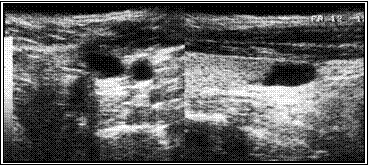

На приведенных ниже эхограммах демонтрируется динамика регрессии в течение года.

Б. Эхограмма через три месяца после склеротерапии

В. Эхограмма через год после склеротерапии. Полная регрессия узла.